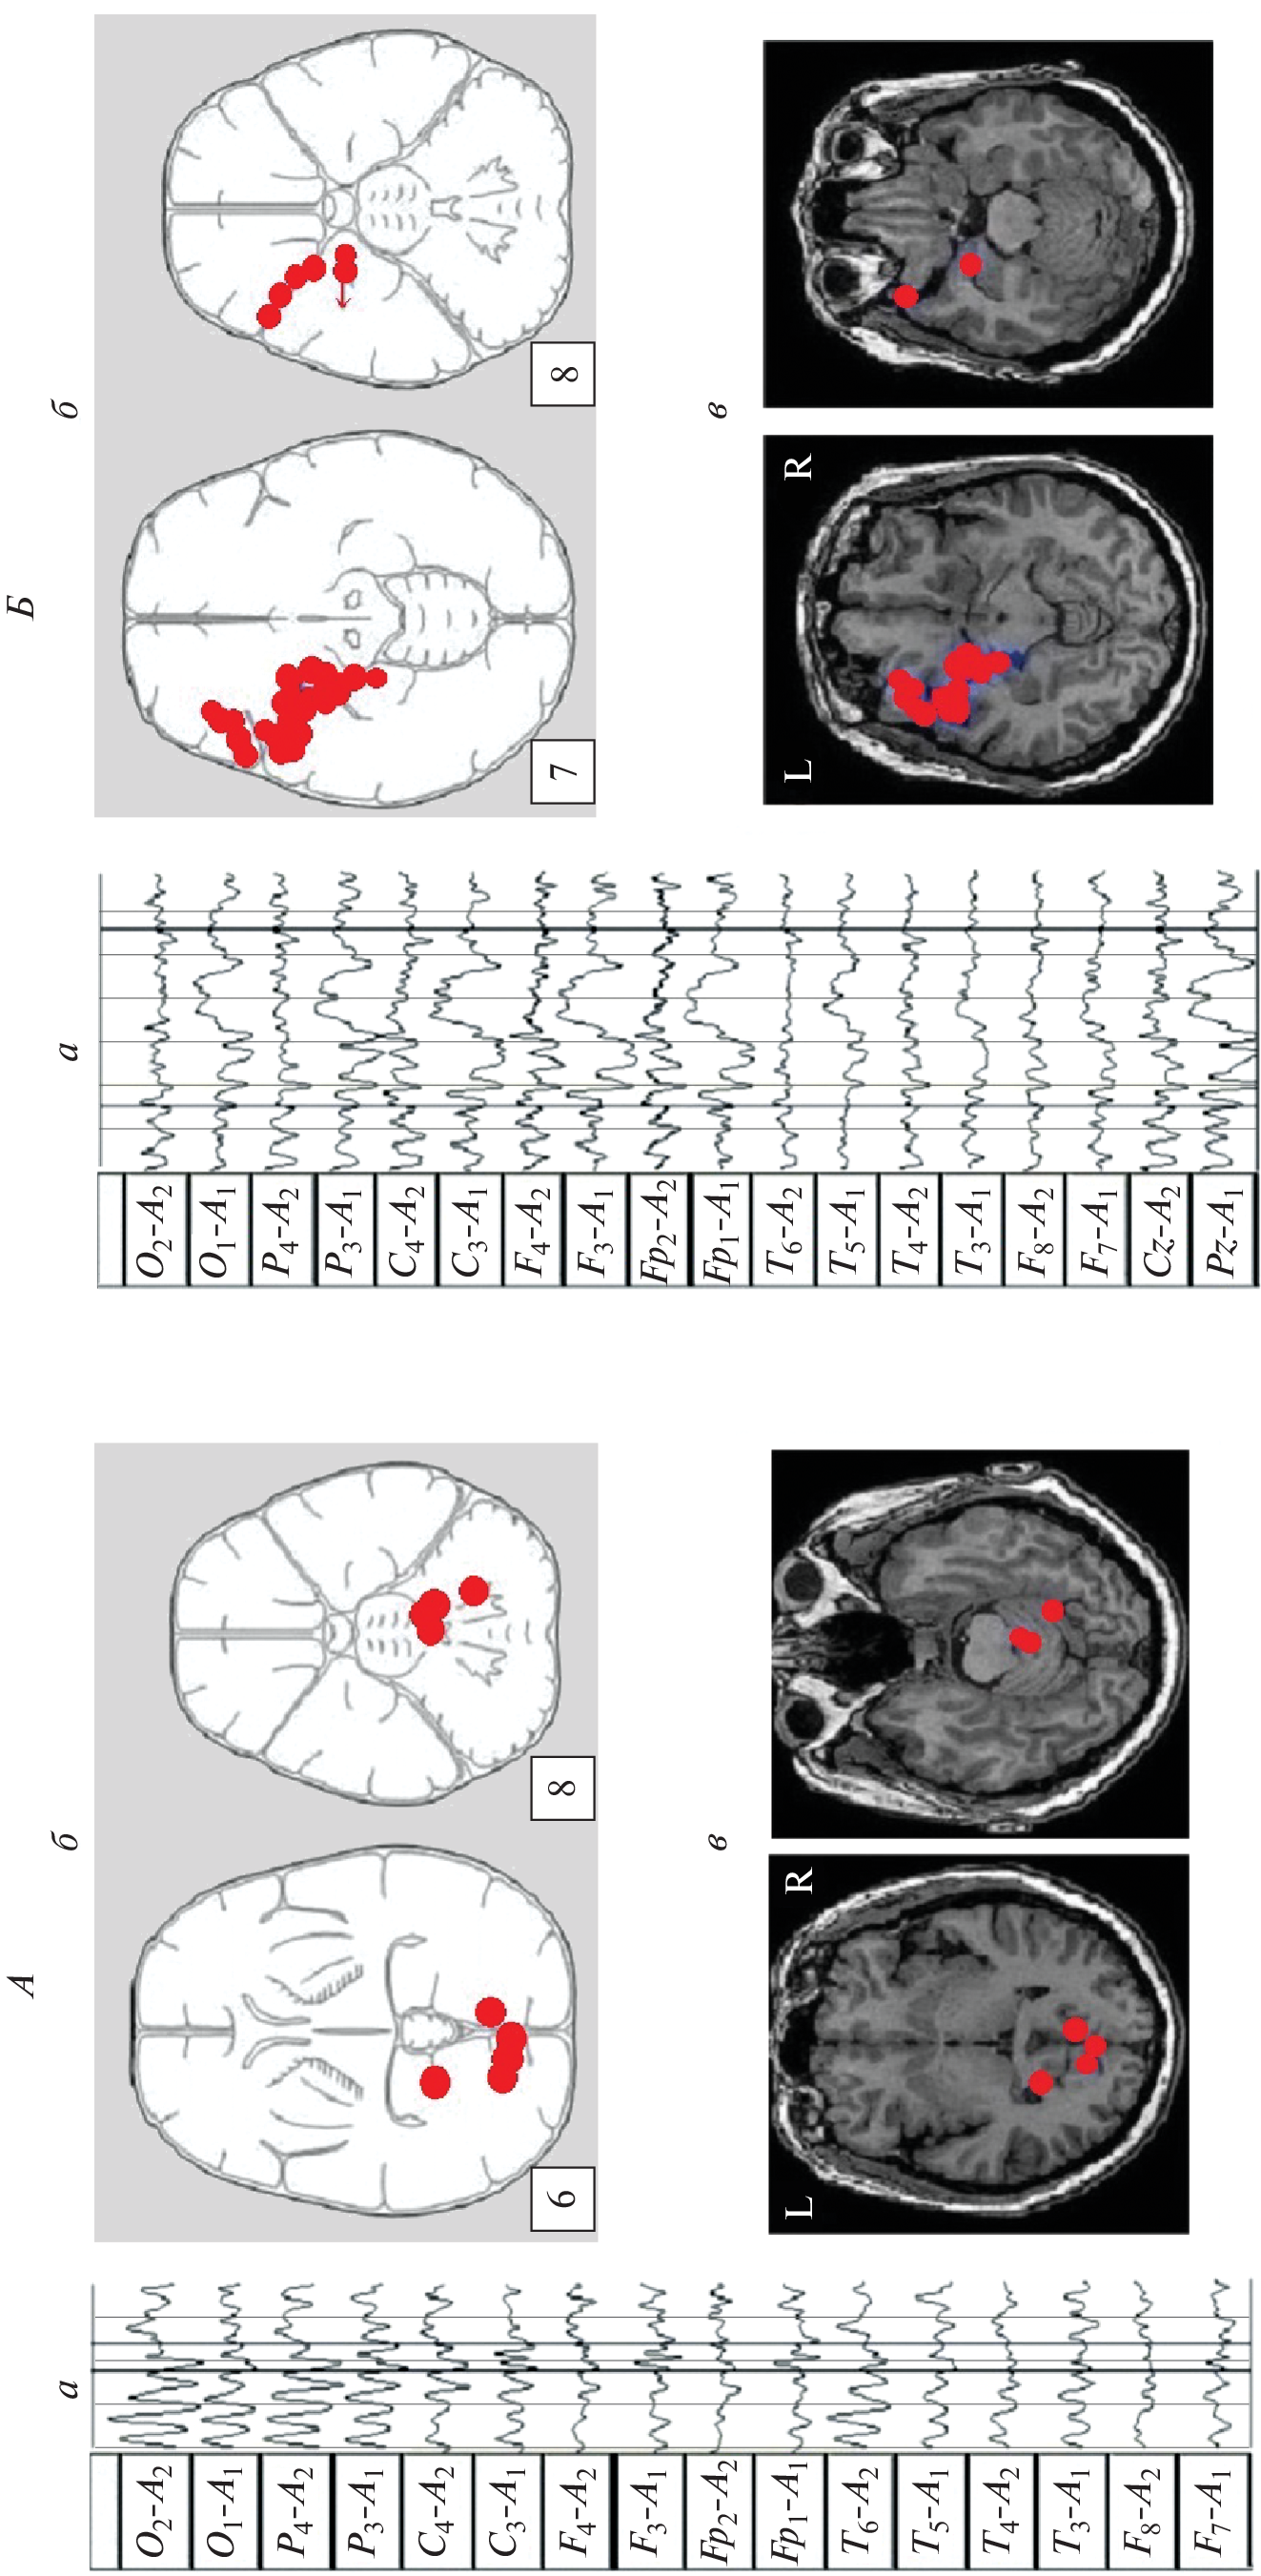

We studied the features of EEG and visual memory processes in 27 patients with a mediobasal regions extracerebral tumor of right and left hemispheres. According to neuroimaging (MRI) and morphometry, the degree of hippocampus involvement in pathological process was assessed. The predominant concentration of irritative-epileptiform signs in the affected hemisphere, as well as the presence of atypical alpha-rhythm episodes in the tumor projection zone, were classified as EEG markers of tumor compressive effect on the hippocampus. Signs of non-identical involvement of the right and left hippocampi in the pathological process were found in the form of a predominance of irritative signs in the left hemisphere throughout the group as a whole. Equivalent dipole sources (EDS) of atypical alpha rhythm are more confined to hippocampal structures than irritative EEG patterns. Neuropsychological testing of visual memory did not reveal significant disturbances in memory processes at this stage of the disease.

- Коптелов Ю.М., Гнездицкий В.В. Анализ “скальповых потенциальных полей” и трехмерная локализация источников эпилептической активности мозга человека // Журн. неврол. психиатр. им. С.С. Корсакова. 1989. Т. 89. № 6. С. 11. Koptelov Yu.M., Gnezditskii V.V. [Analysis of scalp potential fields and the three-dimensional localization of sources of epileptic activity in the human brain] // Zh. Nevrol. Psikhiatr. Im. S.S. Korsakova. 1989. V. 89. № 6. P. 11.

- Болдырева Г.Н. Атипичные формы церебральной альфа-активности при поражении регуляторных структур мозга человека // Физиология человека. 2018. Т. 44. № 3. С. 14. Boldyreva G.N. Atypical forms of cerebral alpha activity when human brain regulatory structures are damaged // Human Physiology. 2018. V. 44. № 3. P. 246.

- Болдырева Г.Н., Шарова Е.В., Коптелов Ю.М. и др. Исследование генеза патологических паттернов ЭЭГ при опухолевом и травматическом поражении мозга человека // Физиология человека. 2005. Т. 31. № 1. С. 24. Boldyreva G.N., Sharova E.V., Koptelov Yu.M. et al. Study of the genesis of pathological EEG patterns in tumor and traumatic lesions of the human brain // Human Physiology. 2005. V. 31. № 1. P. 18.

- Фролов А.А., Болдырева Г.Н., Коптелов Ю.М. Поиск источников патологической альфа-активности ЭЭГ человека при поражении лимбических структур // Журн. высш. нерв. деят. им. И.П. Павлова. 1998. Т. 48. № 4. С. 687. Frolov A.A., Boldyreva G.N., Koptelov Yu.M. [Sources of pathological EEG alpha-activity in patients with lesions of limbic structures] // Zh. Vyssh. Nerv. Deiat. Im. I.P. Pavlova. V. 48. № 4. P. 687.